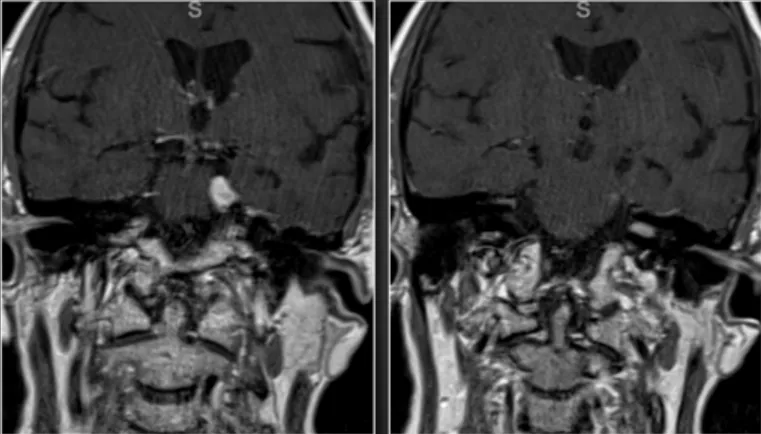

32岁的我,突然的头痛让我深感不适、本以为只是暂时的,所以并没有因为这个去医院,可是没想到头痛越来越严重。 不仅如此,我还出现了其他症状,左眼视野缺损以及闭经。我才32岁,例假...